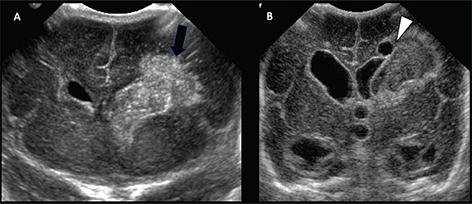

Cranial ultrasound is usually the first brain imaging study performed in neonates for screening if they are symptomatic (39). Although not as sensitive as MRI, large ischemic lesions, perforator strokes, and thrombus in the superior sagittal sinus can be identified. Posterior fossa infarctions are difficult to detect unless quite large, although imaging through the posterolateral fontanelle improves sensitivity. Smaller infarcts in the cerebral cortex or white matter may be difficult to detect (40). The sensitivity for the depiction of perinatal AIS is 68% in the first 3 days, increasing to 87% between days 4 and 10 (41). Cerebral infarction appears as an ill-defined, hyperechogenic focus in a vascular distribution that slowly develops for several days after the event (42). Differentiation of hemorrhagic from bland infarction can be difficult, however, more focal areas of hyperechogenicity within the echogenic area may suggest hemorrhage. Cystic degeneration develops over 2–4 weeks with associated ex vacuo enlargement of the ipsilateral ventricle (Figure 3) (40). Color and power Doppler sonography show changes in regional cerebral blood flow after infarction, as well as asymmetric blood flow with loss of pulsatility in the MCA in the hyperacute phase (43, 44).

Fig 3

Figure 3. Coronal brain US in ex-premature 31-week boy. A. At 11 days of life and (B), 2 weeks later showing evolution of periventricular infarction. Small arrow in (A) indicates an ill-defined subacute infarction in the left frontal white matter. Arrowhead in (B) indicates evolution of infarcted area into the focally cystic encephalomalacia. Case courtesy of Dr. Tamara Feygin, Department of Radiology, Children’s Hospital of Philadelphia.